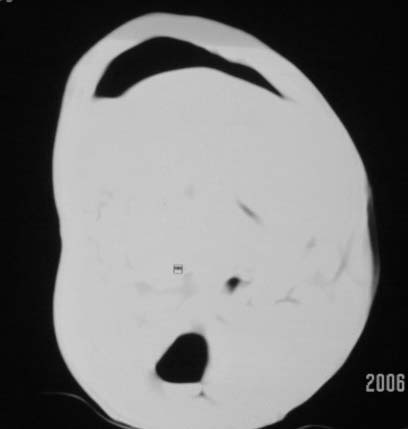

仰卧位见:肝前间隙及肝脾间隙内可见新月形气体密度影,边缘清楚,侧卧位见气体随体位改变而移动,ct值约-929hu。膈下、肝下间隙及部分肠间隙可见液性密度影。考虑:1、上腹部空腔脏器穿孔,以胃穿孔可能性大。2、少量腹水。

仰卧位见:肝前间隙及肝脾间隙内可见新月形气体密度影,边缘清楚,侧卧位见气体随体位改变而移动,ct值约-929hu。膈下、肝下间隙及部分肠间隙可见液性密度影。考虑:1、上腹部空腔脏器穿孔,结合临床,首先考虑胃穿孔可能性大。2、少量腹水

补充--肝门及肝肾间隙以见积气显示。

支持消化道空腔脏器穿孔(腹腔内大量游离气体影,小网膜囊内亦见气体影),少量腹水。